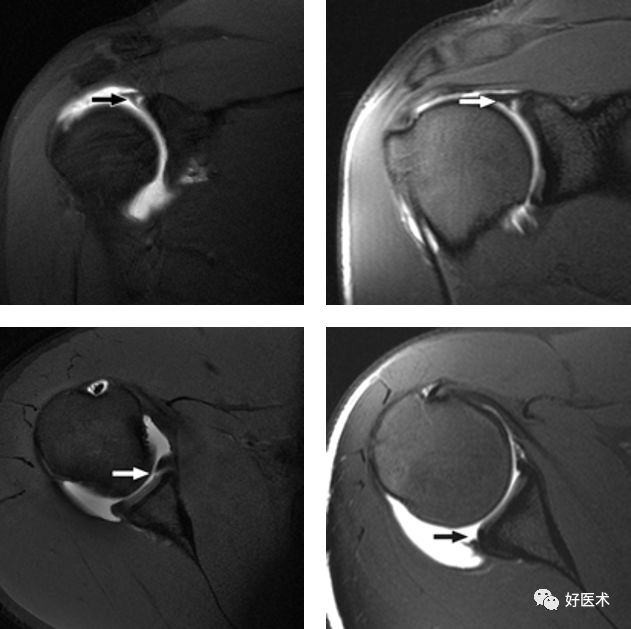

Bankart损伤的MR表现

-

三角形变钝

盂唇撕裂:关节盂唇软骨与盂缘可见线状高信号影并连续到关节面下

盂唇完全消失或盂唇明显移位

若盂唇损伤合并关节盂骨质损伤,称为骨性Bankart病变

骨性Bankart病变

MR间接关节造影1.5T轴位T1W脂肪抑制(TR=460s,TE=90s)

SLAP、Bankart合并Hill-Sach损伤

Hill-Sachs损伤

Hill-Sachs损伤:肩关节前脱位时,肱骨头撞向关节盂缘可导致肱骨头的后外侧的嵌插骨折

MR间接关节造影1.5T轴位T1W脂肪抑制

MR间接关节造影1.5T冠状面T1W脂肪抑制

Hill-sachs,Bankart,关节囊损伤